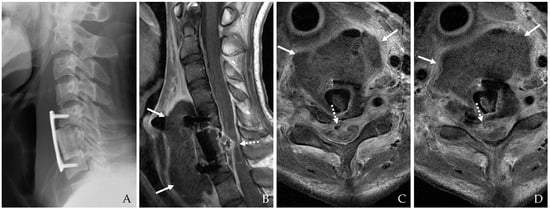

4.1.3. Contrast Esophagography

Contrast esophagography remains a cornerstone in diagnosing esophageal perforations and fistulas. The procedure involves using either barium or Gastrografin contrast agents to visualize the integrity of the esophageal lumen [18,22,23]. Although Gastrografin is generally preferred due to its lower risk of mediastinitis if extravasation occurs, barium is utilized in select cases because of its superior sensitivity [19,23]. This procedure is beneficial for detecting small leaks and determining the extent of perforation (Figure 4). Dynamic swallow studies and functional assessments are increasingly incorporated to provide a comprehensive evaluation of esophageal integrity and function [21].

Figure 4. The patient underwent C5-6-7 anterior cervical corpectomy and fusion (A,B). At postoperative 3 days, postoperative infection occurred, and contrast esophagography showed esophageal rupture with dye leakage (C). Therefore, the patient underwent irrigation/debridement, removal of plate and screws, primary repair of esophageal rupture, and C3-4-5-6-7 posterior fixation (D). However, the patient died due to sepsis.